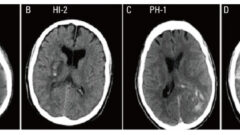

救急外来における出血性梗塞のマネジメント

出血性梗塞は発症しばらくしてからの合併症であるため救急外来で遭遇する機会は少なめですがその分、救急医が初療のことをよく理解していないことが多いためまとめました。